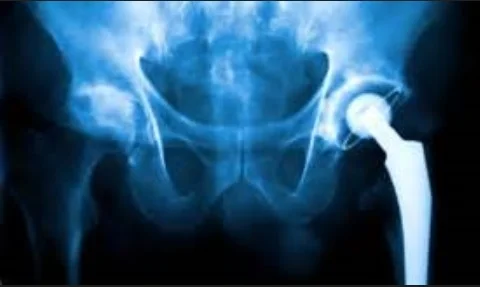

Simfini-IMPLANT

Orthopedic surgeons select joint hip implants based on X-ray scans. There are about 400,000 surgeries per year in the US, of which 15% are revision surgeries. Simfini-IMPLANT analyzes the bone-implant structure and selects a patient-specific implant (among all available implants in the specific hospital) that is biomechanically appropriate for the specific patient. This improves the surgical outcome by improving a patient’s quality of life and reduces the expense of treatment.